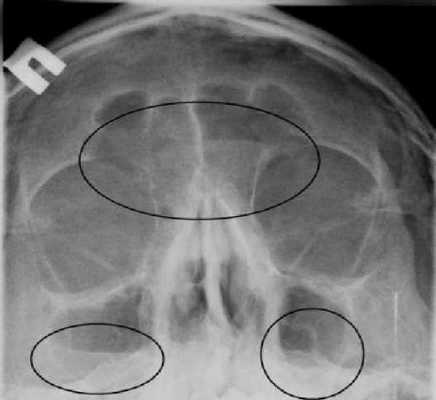

Фото снимка здорового человека

Рентген пазух носа здорового человека выглядит так:

- Носовая перегородка разделяет носовую полость на симметричные стороны треугольника.

- Белые полосы, проходящие справа и слева разделенной области — это носовые ходы.

- Треугольные полости по бокам носа — гайморовы пазухи.

- Между глазницами расположена решетчатая пазуха с тонкими стенками, ячейки которой должны хорошо просматриваться.

- Выше глазниц определяются лобные пазухи, которые могут иметь различную форму. Допускается их разделение костными перегородками.

- В пазухах должен находиться воздух. Их края, как и контуры костей, должны быть четкими и ровными.